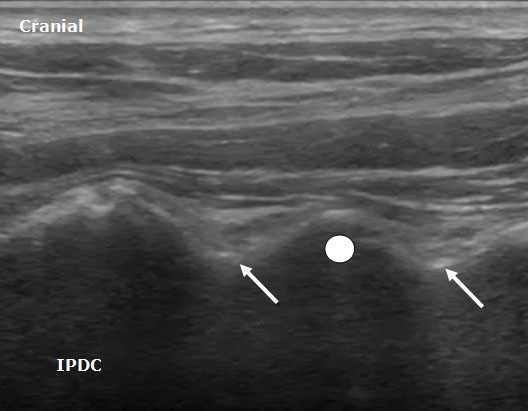

A high frequency linear array transducer is needed for visualization of the cervical medial branches and facet joints. Multiple ultrasound techniques have been described to visualize the cervical facets and associated medial branches.[5-9] The first technique involves positioning the patient in the lateral decubitus position.[7] Initially the transducer is placed over the mastoid process in the longitudinal axis. The transducer position is optimized to view the transverse processes of C1 and C2. The vertebral artery between C1 and C2 can often be visualized. Next, the transducer is moved posteriorly and caudad in the longitudinal plane. The third occipital nerve is identified. The third occipital nerve exists 1 mm from the bony elements. Once the third occipital nerve has been identified and the associated C2-C3 facet, these landmarks can be used for counting as the transducer is moved caudad over the remaining cervical facet joints (Figure 2). The remaining cervical medial branches are identified around each respective neck of the articular pillar (i.e. depressed area). The nerves typically are hypoechoic structures with internal hyperechoic areas (Figure 3).

Figure 3. A longitudinal ultrasound image of the cervical spine demonstrating the cervical medial branches (arrows) and associated cervical facet joint (circle).